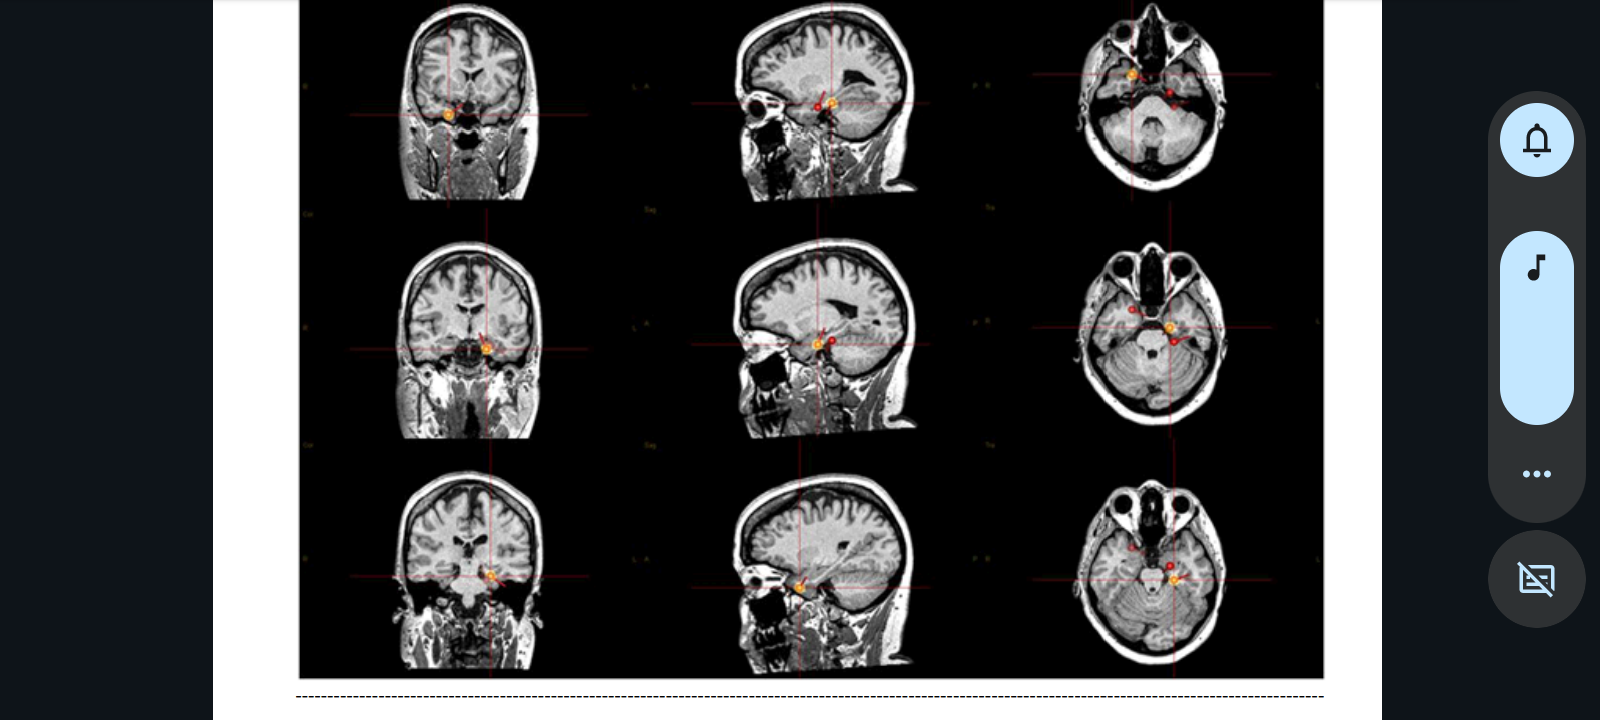

Since about 2020, I started having primarily nocturnal seizures. Now, for the past couple or so years, I've been unable to work due to more common not-whilst-asleep ones. I'd always had tonic-clonic amongst other types before but primarily whilst asleep. Thankfully, I finally got my craniotomy performed last February and it has helped but not fully erased all neurological symptoms I deal with.

Post-surgery a few months later, I had my second weeklong stay in the neurological department with nonstop video and EEG monitoring.

During my stay, I had a few irregular occurrences (followed by usual post-epileptic symptoms including one where I stayed conscious and it lasted an hour long). But the occurrences did not show up on the EEG as they did for the handful of times during my previous/first time staying in the unit – Thanksgiving week, the year before last.

These occurrences were deemed to be non-epileptic symptomatic, which my neurologist would later explain to me is not very uncommon for those like myself (those post-surgery) – yet given the symptoms and how strong of medications I am to remain on – I am not able to work. I deal with extremely strong drowsiness caused by the medications I have to take – causing me to sleep for hours at a time post-medicine-taking on top of condition-caused fiery headaches, constant ear ringing, lightheadedness, brain fog, and more.